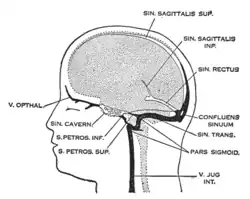

The sinuses at the base of the skull. (Visible as light blue circle at center.) | |